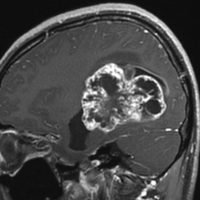

第4脳室上衣腫(良性と言える思春期例:EPN-PFB)

青年に発生したものです。かなり分化度の高い延髄背側 ovex 発生の上衣腫です。境界が明瞭なのですが,実際に側方(延髄小脳脚槽)で椎骨動脈や後下小脳動脈,下位脳神経に癒着しているので剥離は必ずしも容易ではありません。この例では幸い全摘出できました。

摘出した標本のHE染色です。左側ではperivascular pseudorosette(血管周囲の無核野)がみられ,右側ではependymal tube (ependymal canal) が認められます。

左がGFAP染色、右がMIB-1(Ki-67)染色です。 GFAPは腫瘍血管の周囲の無核野に強陽性です。MIB-1 labelling index が1%以下であり,この上衣腫の増殖能が極めて低いことを示しています。このような高分化型で増殖能の低い上衣腫は脊髄髄内には多いのですが,脳では珍しいものです。ovex中心上衣腫にみられます。